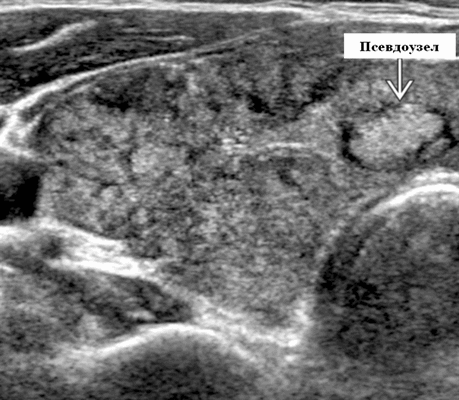

При ультразвуковом исследовании при АИТ обычно отмечается понижение эхогенности железы и появление выраженных диффузных изменений. Переводя на «человеческий» язык, можно сказать, что при аутоиммунном тиреоидите щитовидная железа выглядит на экране УЗИ-аппарата темной и имеет очень неоднородную структуру - в одних местах ткань более светлая, в других - более темная. Нередко врачи ультразвуковой диагностики обнаруживают при болезни Хашимото в ткани щитовидной железы и узлы. Следует отметить, что зачастую эти уплотнения настоящими узлами не являются и представляют собой просто очаги с резко выраженным воспалительным процессом, их еще называют «псевдоузлами». Чаще всего квалифицированный врач ультразвуковой диагностики может отличить псевдоузел при аутоиммунном тиреоидите от узла, однако в некоторых случаях сделать это непросто. Именно поэтому врачи нередко пишут заключение примерно так: «Признаки АИТ. Узлы (псевдоузлы?) щитовидной железы», чтобы подчеркнуть свою неуверенность в оценке характера изменений. При выявлении в ткани щитовидной железы на фоне аутоиммунного тиреоидита образований диаметром 1 см и более пациенту рекомендуется проведение биопсии для уточнения их природы. В ряде случаев после получения результатов исследования становится понятно, что исследованный узел является псевдоузлом на фоне АИТ (ответ цитолога обычно в таких случаях краток: «Аутоиммунный тиреоидит» или «Тиреоидит Хашимото»). Вместе с тем, на фоне аутоиммунного тиреоидита возможно выявление и узлов коллоидного (доброкачественного) строения, и злокачественных новообразований.

- Гипертрофический тиреоидит (с увеличением щитовидной железы) = тиреоидит Хашимото, причём чаще встречается узловая (правильнее сказать «псевдоузловая форма» *), размеры железы могут достигать более 80-100 мл в объёме.

Псевдоузлы при АИТ - это очаги с выраженным воспалительным процессом. - Атрофический тиреоидит (с уменьшением железы менее 4.5 мл в объёме - это сумма объёма обеих долей), который надо дифференцировать с врождённой гипоплазией щитовидной железы